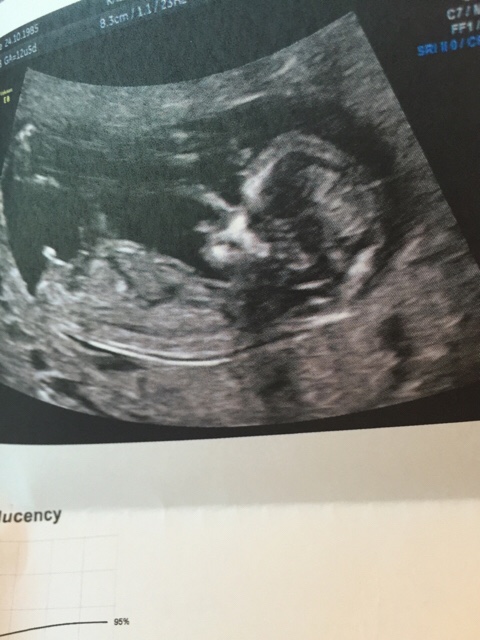

Ble satt to dager tilbake, men kan nok stemme med de norske sidene :) så jeg er idag 12+6 og termin 14 juni :) var på ultralyd idag og så ingen tegn til hvorfor jeg blør inni mellom ❤️

Men det viktigste av alt så var babyen i topp form og hadde det supert inni magehuset. Lykke!!!! Ikke bare det men mest trolig blir det en GUTT!!! Han sa at det var 80 prosent sjans, så ville avventet med innkjøp :) så utrolig spennende!!!! Jeg som var sikker på at det ble bare jenter her i hus! :) viss det blir gutt har storesøster hatt rett med Elvira og babyen i magen! ;)